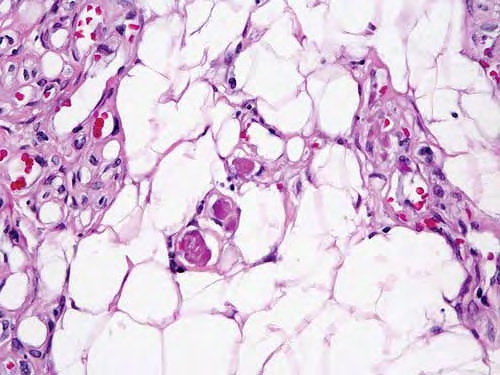

Angiolipoma = الشحموم الوعائي